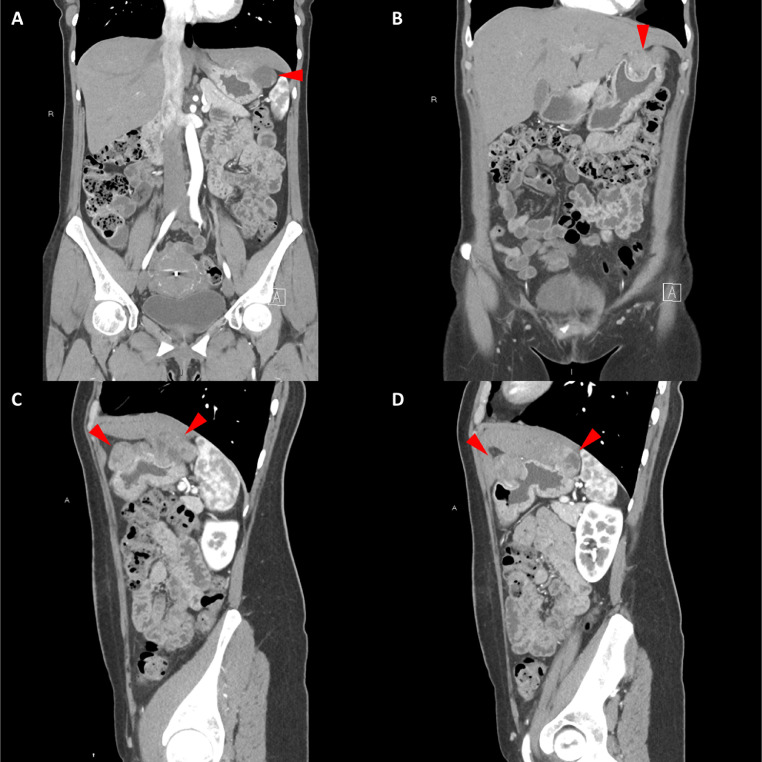

頸部增強 CT 顯示 2 個強烈強化的腫塊。 一個位于頸部右側,位于右側頸內動脈后方的頸動脈間隙中,位于莖突內側,大小為 24 × 24 × 30 mm,頸靜脈橫向移位(圖 1A)。 第二個位于左側頸動脈間隙,在分叉處正上方展開頸外動脈和頸內動脈,尺寸為 15 × 18 × 22 mm(圖 1B)。 影像學檢查結果與右側迷走神經和左側頸動脈體副神經節(jié)瘤一致,與之前的活檢結果一致。

Fig. 1

圖1:右側迷走神經和左側頸動脈體副神經節(jié)瘤。 (A) 軸位增強 CT 顯示右側頸動脈間隙、右側頸內動脈后方(白色箭頭)和莖突內側有強烈強化的腫塊(紅色箭頭)。 (B) 軸位對比增強 CT 顯示左頸動脈間隙有強烈強化的腫塊(紅色箭頭),向后張開頸內動脈(紅色箭頭),向前張開頸外動脈(紅色箭頭)。 (C) 冠狀對比增強 CT 顯示兩個增強腫塊(紅色箭頭)。